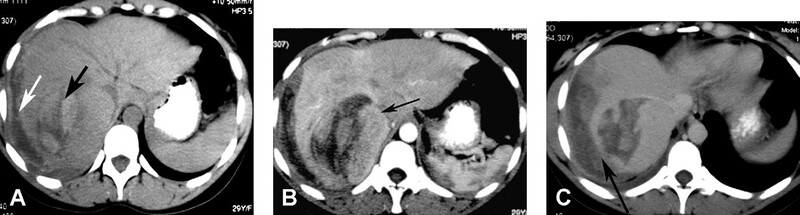

Nói chung, HCC tăng tín hiệu trên T2W và giảm tín hiệu trên T1W. Hình MRI sau tiêm thuốc thấy bắt thuốc thì động mạch rõ rệt, không đều, thải thuốc nhanh ở thì tĩnh mạch và thì muộn (Hình 11). Phát sinh bắt thuốc viền ngoại vi do giả bao. Nốt loạn sản độ cao có thể bắt thuốc. Tuy nhiên, nốt loạn sản không có bao giả. HCC lan tỏa có tín hiệu không đồng nhất trên T1W và T2w, với bắt quang không đều, có các vùng thải thuốc và các vùng khác có thể còn đọng thuốc. Huyết khối do u ở tĩnh mạch cửa cho thấy bắt quang ở thì động mạch điển hình (Hình 10 và 11). Dấu hiệu này giúp phân biệt huyết khối do u với huyết khối lành tính, không bắt quang ở thì động m ạch. Bao u có thể thường gặp ở người châu Á, là các viền echo trống trên siêu âm và bắt thuốc viền ngoại vi ở thì trễ trên CT và MRI.

Hình 11. Bệnh nhân nam 62 tuổi xơ gan và carcinoma tế bào gan thâm nhiễm lan tỏa (cùng bệnh nhân ở hình 10). Khối giảm tín hiệu (mũi tên) trên hình T1W 3D GRE (A) và tăng tín hiệu (mũi tên) trên hình T2W SSFSE (B). Khối bắt thuốc không đồng nhất (mũi tên) ở thì động mạch với bờ lan tỏa (C). Huyết khối do u bắt thuốc không đồng nhất (D, mũi tê n) phình lớn tĩnh mạch cửa và lan vào hợp lưu tĩnh mạch mạc treo tràng trên (E, m ũi tên). Thì muộn (F) thấy u thải thuốc kèm bắt thuốc vách bên trong (mũi tên) và giả bao.